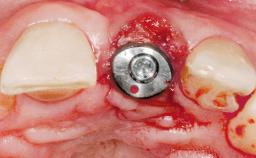

A 30-year-old female patient had lost tooth 21 and was referred to our clinic for consultation and treatment. Due to advanced apical infection, tooth 21 had been extracted two months earlier at another clinic and an acrylic-resin tooth had been bonded to the adjacent teeth. The patient desired implant treatment to avoid any damage to the adjacent natural teeth. While the patient had no history of any systemic disorder, she was a heavy smoker and exhibited medium to advanced periodontitis in the entire jaw. After the initial treatment to achieve a pocket probing depth of less than 4 mm and no bleeding on probing, a decrease in the height of the papillae mesial and distal to the extraction site and overall gingival recession were observed.

Type of Implants One-Piece|Reduced-Diameter

Attachment One-Piece|Reduced-Diameter

Bone Augmentation Horizontal|Staged

Augmentation Materials Autogenous chips|Membrane

Soft Tissue Grafting Simultaneous

Defining Characteristics One missing tooth to be replaced by an implant-borne prosthesis

Placement Protocol Early or late implant placement